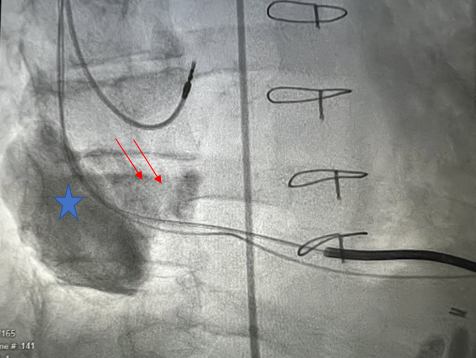

Coronary angiogram showed a large aneurysm in SVG-RCA with a fistula between the SVG to right atrium (RA) (Figure 1, Video). Right heart catheterization demonstrated elevated right-sided and left-sided filling pressures with no step up on oxygen saturation, suggesting bidirectional shunting. However, given the risk of aneurysm rupture, assessment using computed tomography (CT) showed the aneurysm measurements of 5.6 x 5.9 cm in diameter with SVG measuring 8 mm proximal to the aneurysm (Figure 2).1,2 Thallium study was performed and showed no viability in the inferior wall territory.